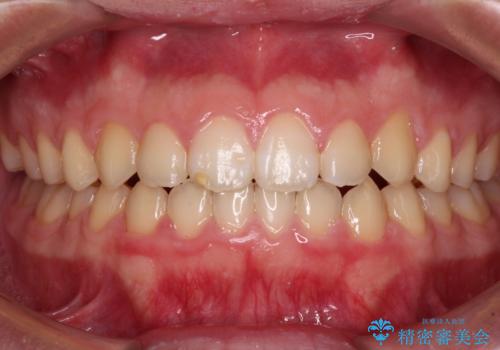

- 下顎前歯が抜けそうとのことで来院された患者様です。

初診の状態ではすぐにでも抜けそうな状態で、インプラントによる補綴治療を行うこととしました。

インプラント治療に際し、前歯の叢生に対する矯正治療を提案したところ、興味を持たれたので、インビザライン・ライトによる矯正治療を行うこととしました。

抜歯後にスペースができると恥ずかしいため、抜歯した歯を接着剤で固定した上で矯正治療を行い、その後インプラントやオールセラミッククラウンの装着を行うこととしました。